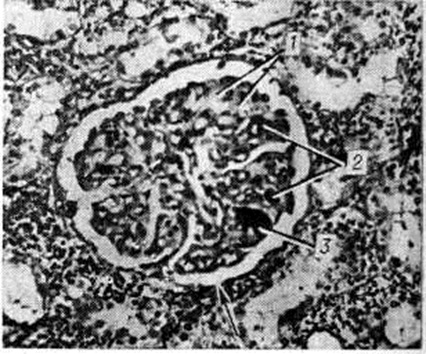

При длительности заболевания более 2 месяцев наряду с фибриноидными изменениями выражены пролиферативные и склеротические. Гематоксилинофильные зернистые массы в сосудах, дающие отрицательную реакцию Коссы на известь и названные Прокшом и Томси (P. Proks, F. Tomsi, 1955) ложноизвестковыми зёрнами, могут быть скоплением микробов или продуктами гемолиза. Они часто встречаются в капиллярах почечных клубочков наряду с фибриноидным некрозом капиллярных петель и окклюзией их эозинофильными массами (рис, 2). В печени, почках, селезёнке, костном мозге, лимфатических, узлах с помощью реакции Перльса обнаруживают скопления гемосидерина. В костном мозге п селезёнке количество плазматических клеток увеличено.